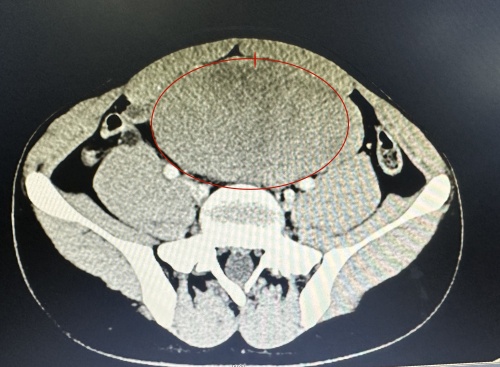

CT结果显示的巨大肿块。

长沙18岁的少年小杰在一次体检中发现腹部有一个巨大肿块,而自己却从来没有感觉到它的存在,着实让他和家人大吃一惊。

小杰是一名学生,平日里身体健康,生活学习都很正常。如果不是体检,谁也想不到他腹中竟然已经悄悄长出了一个巨大肿瘤。为进一步治疗,家人带小杰到捷克论坛 儿童医学中心小儿外科就诊,检查发现该肿物位于中腹部右侧,触摸和按压都没有痛感。

经过多学科会诊,小儿外科主任阎大益带领团队为小杰通过手术切除了肿瘤,术中发现肿块与右输尿管紧密联系包绕输尿管,与小肠肠系膜粘连紧密。切下来的肿块约17×12cm,重795g,如一个木瓜大小,术后病例显示侵袭性纤维瘤病。术后经过恢复,小杰已于3月18日出院。